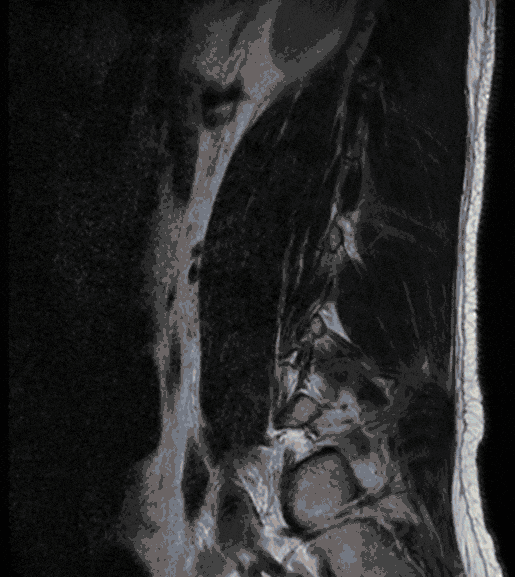

Gelenkzysten treten meist in Folge einer degenerativen Erkrankung der Wirbelgelenke (Facetten-Gelenke) auf und können Ausdruck einer Instabilität sein. Da Gelenkzysten zu einer deutlichen Einengung des Wirbelkanals führen können, können sie mit Beschwerden einhergehen, die einer Spinalkanalstenose gleichen.